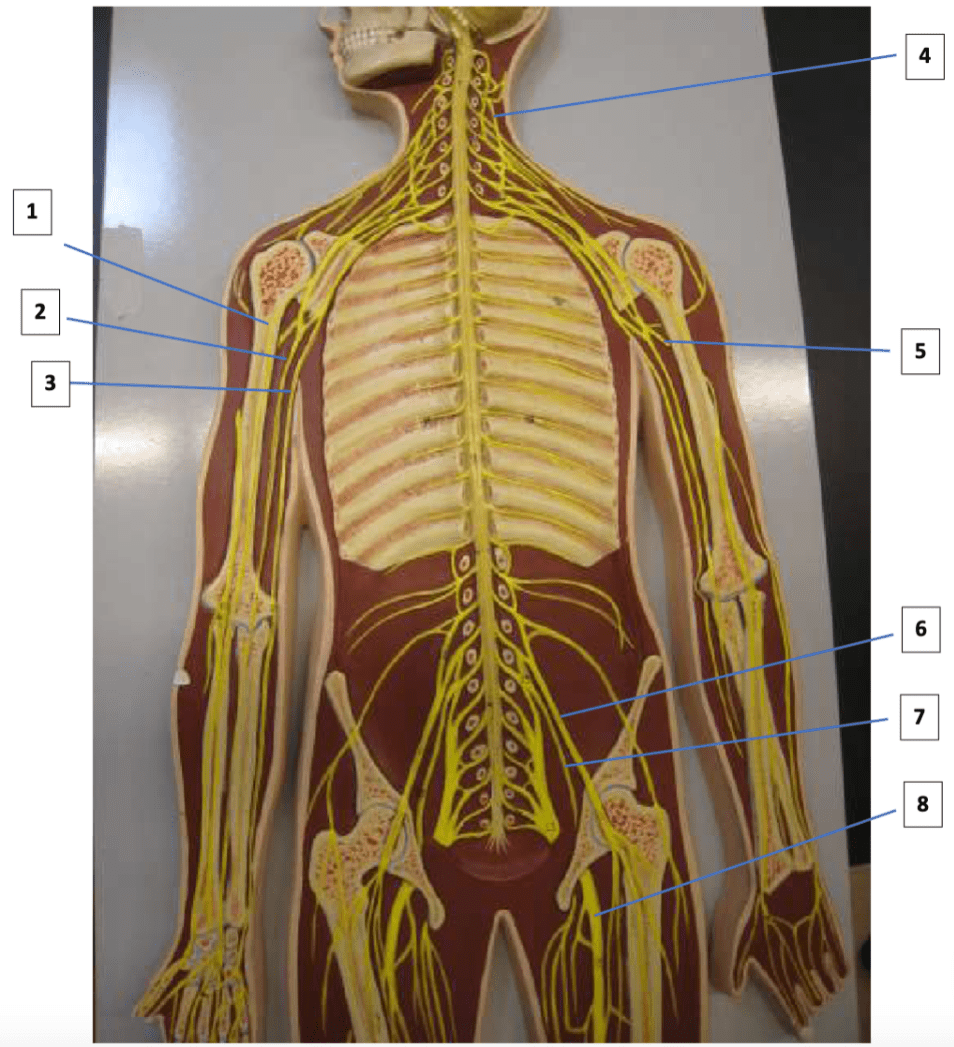

Label 2, 4, 8

2: Median nerve

4: Phrenic nerve

8: Sciatic nerve